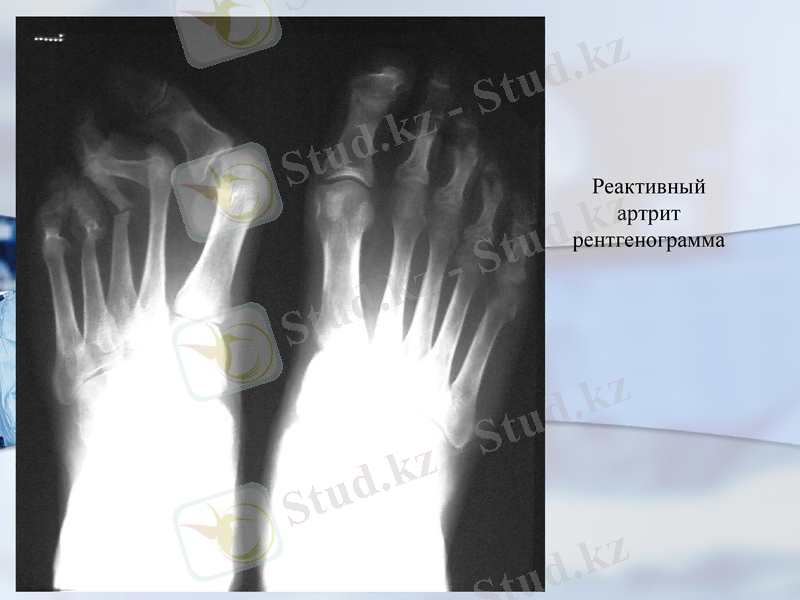

Реактивный артрит рентгенограмма

1. Рентгенография